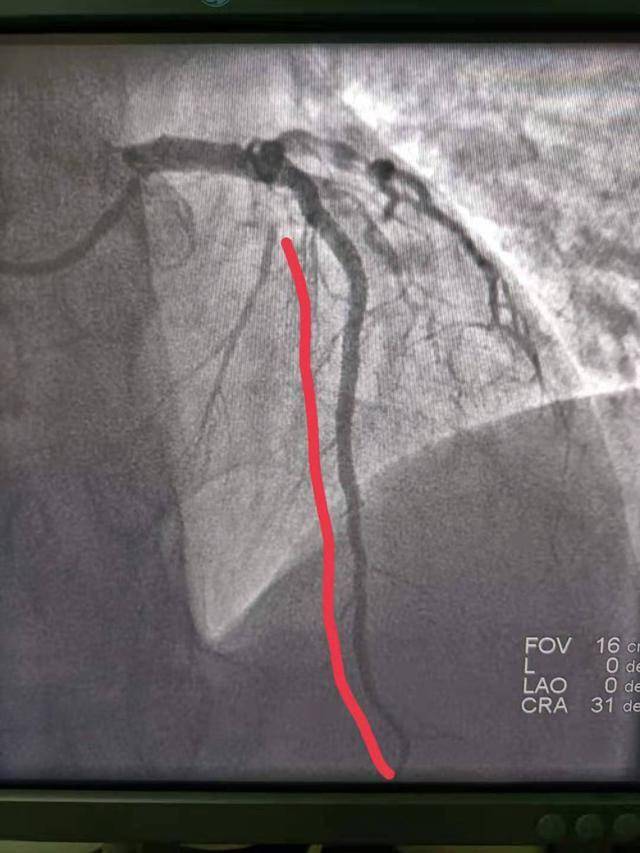

今日关注抢救心梗患者延续最美曲线

图片尺寸960x1280